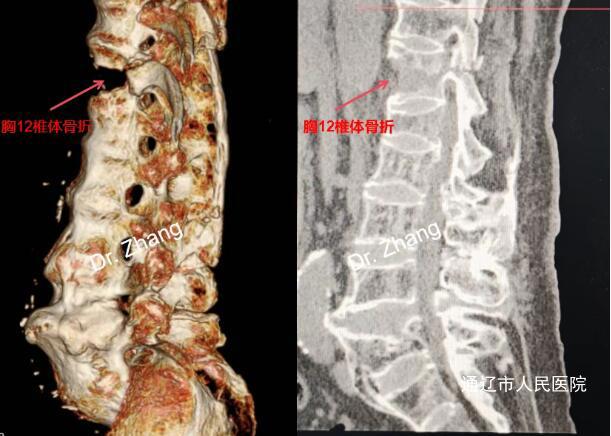

近日,我院脊柱外科成功为一名近90岁高龄的强直性脊柱炎合并重度骨质疏松患者实施胸椎骨折内固定手术。患者因跌倒导致高风险"Chance骨折"(椎体不稳定型骨折),随时可能因骨折移位压迫脊髓导致截瘫。

Chance骨折属于脊柱"不稳定型骨折",患者已出现椎体移位,若不及时手术,脊髓可能进行性损伤导致永久性瘫痪。另外高龄患者长期卧床易引发肺炎、血栓等致命并发症,手术是唯一能早期活动、改善预后的选择。

1、脊柱解剖变异:强直性脊柱炎患者椎体融合、韧带骨化,置钉通道狭窄,毫米级误差都可能损伤神经。